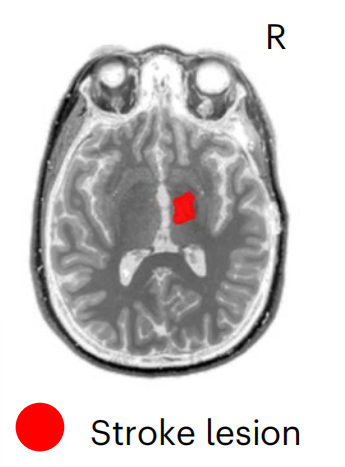

病例1:女,31歲,在參與該研究的九年前,因海綿狀畸形繼發(fā)于右側(cè)丘腦出血性中風,病變局限于內(nèi)囊、中腦和腦橋,F(xiàn)AS=0.17,F(xiàn)ugl-Meyer運動評估顯示中度損傷。 病例2:女,47歲,在參與本研究的三年前,因右頸動脈夾層導致右側(cè)缺血性大腦中動脈(MCA)卒中,導致大面積MCA梗死。SCS01的,病變范圍較大,影響右半球的放射冠,F(xiàn)AS=0.35,F(xiàn)ugl-Meyer運動評估顯示重度損傷。 SCS01 SCS02 治療方案